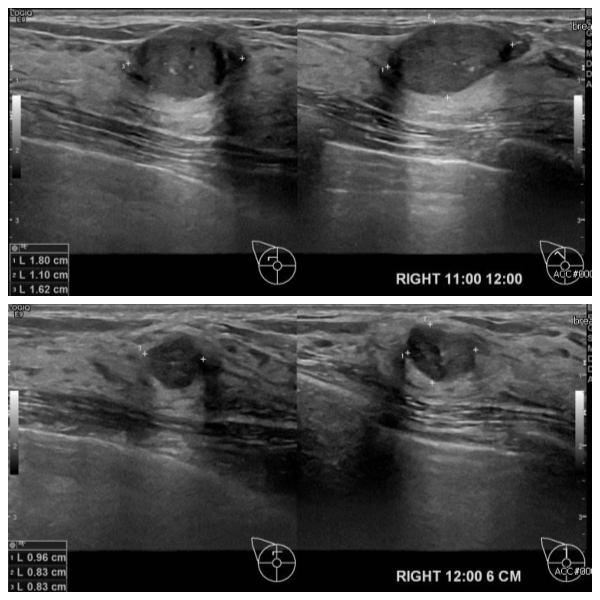

상기환자 우측 유방에 만져지는 멍울로 내원하신 30대 여성분으로 본원 초음파상 우측 11시에서 12시 방향에 의심스러운 멍울과 우측 12시 방향에서 6cm 떨어진 거리의 멍울 조직검사 시행하여 두곳모두 점액암 진단 되었습니다.